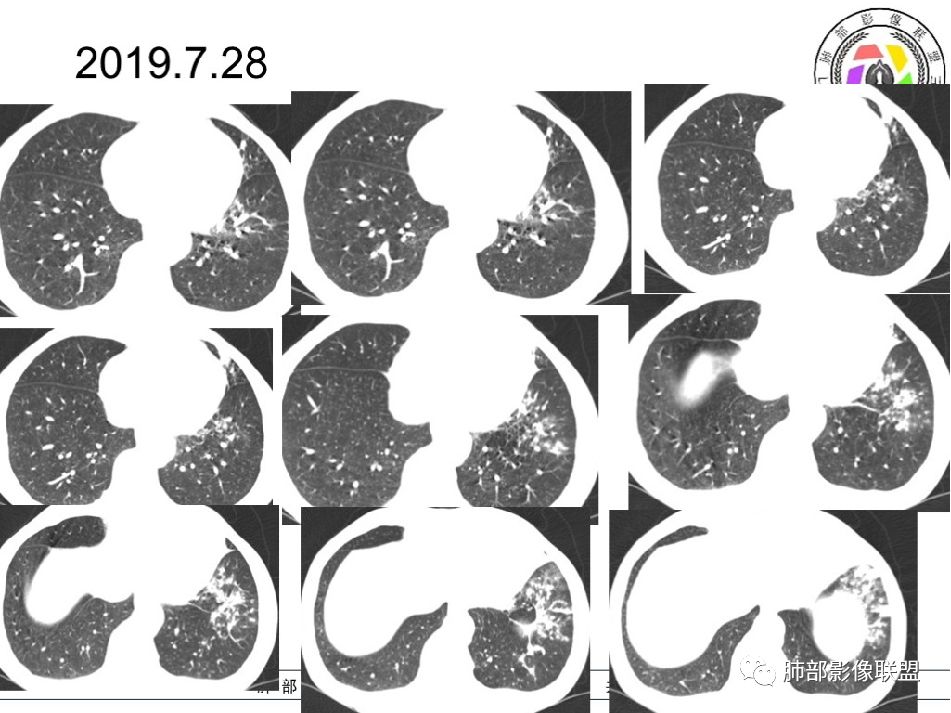

2019-7-28CT左肺病变较前进展(下肺为著,多为新发),左上肺空洞较前增大;

第二次住院(8.1-8.27):哌拉西林他唑巴坦抗感染10天复查,左肺病变进展,左上肺空洞缩小;改为DL2EMFX抗结核护肝;IgM(-),免疫球蛋白E1090.0IU/ml,病情好转出院。

2019--9-30复查CT:与2019-8-12比较,左下肺后外基底段较前吸收减少。(有效)但前内基底段病灶较前增多,原空洞无变化,其下方病灶内新发空洞与原空洞相连,10.5*6.4mm,(小空洞),(无效?)。

思维过程:2019-10-8小空洞,2019-7-28是不是也有?二元论解释,结核,有效;但又新发有新病灶,空洞前期变大;上腹部隐痛,手指关节间断痛,IgE是不是明显增高,有意义?